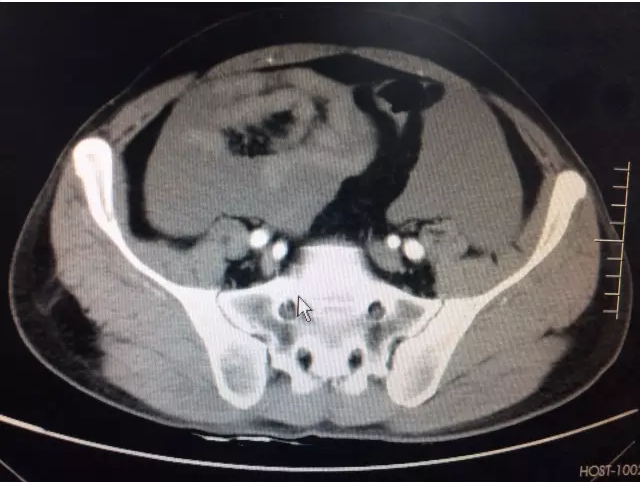

科主任崔小兵主任医师诊视患者后指出:“诊断考虑胃大弯占位:间质瘤可能,目前患者腹痛剧烈,有腹膜炎体征,不排除有肿瘤破裂可能,急查腹部CT,完善相关化验检查,尽早手术。”紧急动员之后,管床医生及护士密切合作,启动急危重症患者工作流程,全程陪同外出检查,结果提示:1.胃巨大占位;2.盆腹腔大量积液,考虑胃间质瘤破裂;3.失血性休克代偿期(患者心率102次/分,血压105/74mmHg)。主任当机立断,要求紧急联系麻醉科、输血科,拟于假期前一天急诊手术探查。

术前CT提示盆腔大量积液